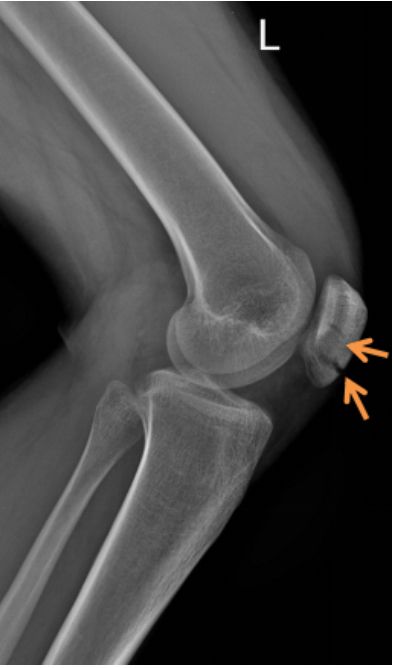

易误诊为骨折的二分髌骨